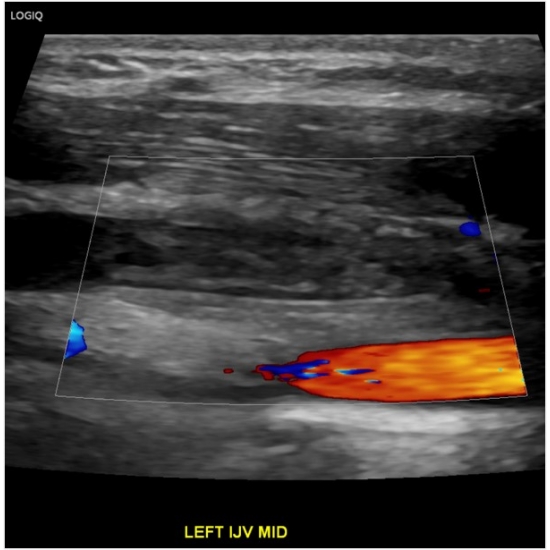

Given her significant neck swelling, ED providers ordered venous doppler ultrasound of the upper extremities.

Venous Doppler of the Upper Extremity bilateral: Occlusive thrombus within the left internal jugular vein measuring approximately 3.1 cm length. Case Photo #10 , Case Photo #2 and Case Photo #3